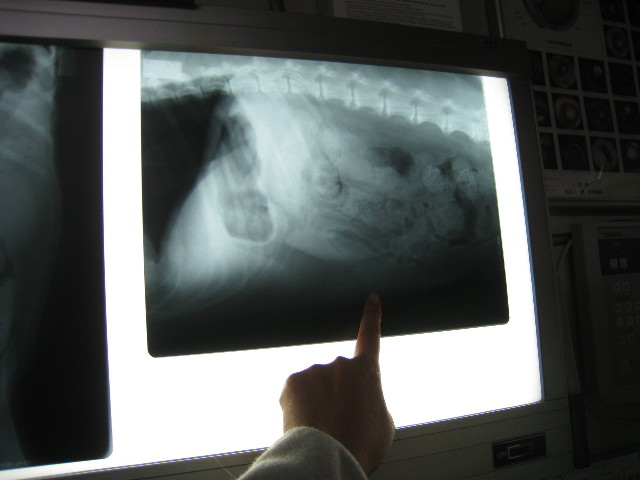

腹膜炎になってしまっていないかどうかを診る為にレントゲンを撮った。

腹膜炎になっていると、曇りガラスのように写るらしいが、

●べべは腹膜炎にはなっていない

指のあたりがおへそ。

●おへその上の臓器が通常より上にあがってしまっているので、おへそと臓器の間に何かある?